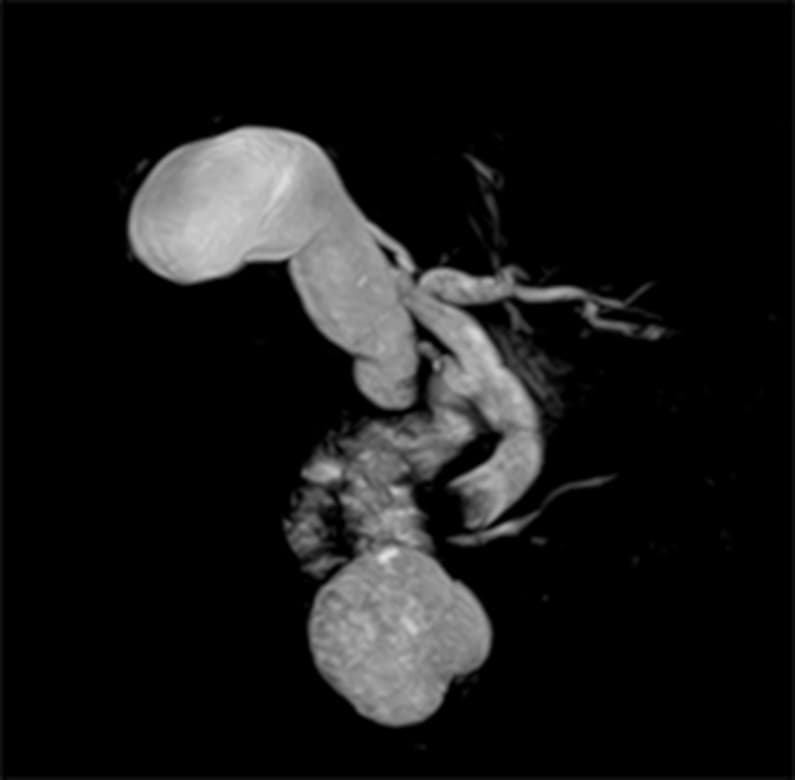

CT検査(膵臓)